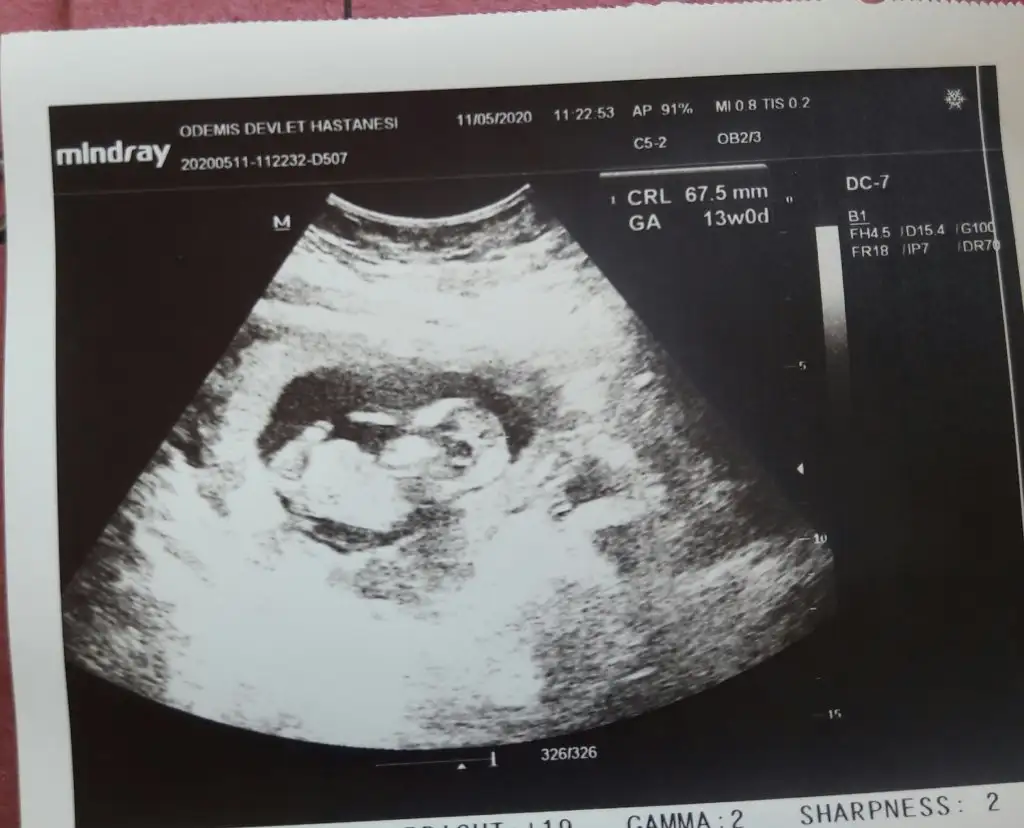

Tamamdır teşekkürlerKız gibi sanki 13 hafta olursa paylaşın

Sanki kız gibi emin olamıyorum çok net değil beyaz usg başka varsa paylaşın 11 12 de olabilirEki Görüntüle 2633651 13 haftalık nub bakarmısınz rica etsem

Başka usg varsa paylaşan 13 haftada olabilir sanki emin değilim kız gibi gibiBenim ultrason sonucunuda yorumlarmısnız

Bebeginiz kızmıAslında eminde olamadım nubu ne dik nede paralel tam karşıya bakıyor tekrar tekrar usg baktım başka usg varmı olursa paylaşın 13 de olursa paylaşınböyle usg ler yanıtıyor beni